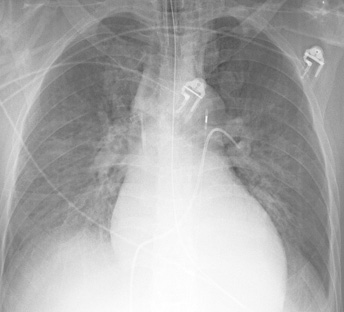

| One of the most effective but least appreciated tools is the grease pencil. Mark up the films. On portables, mark the end of all the lines and catheters. Mark the carina. Mark the edge of the pneumothorax. Outline collapsed lobes and anything else which you feel important. Why? IRed marks help convey what's important. There's a more subtle message that is also relayed. I've been there. I'm involved. I have an interest in patient care. Which brings up the story of kilroy. |